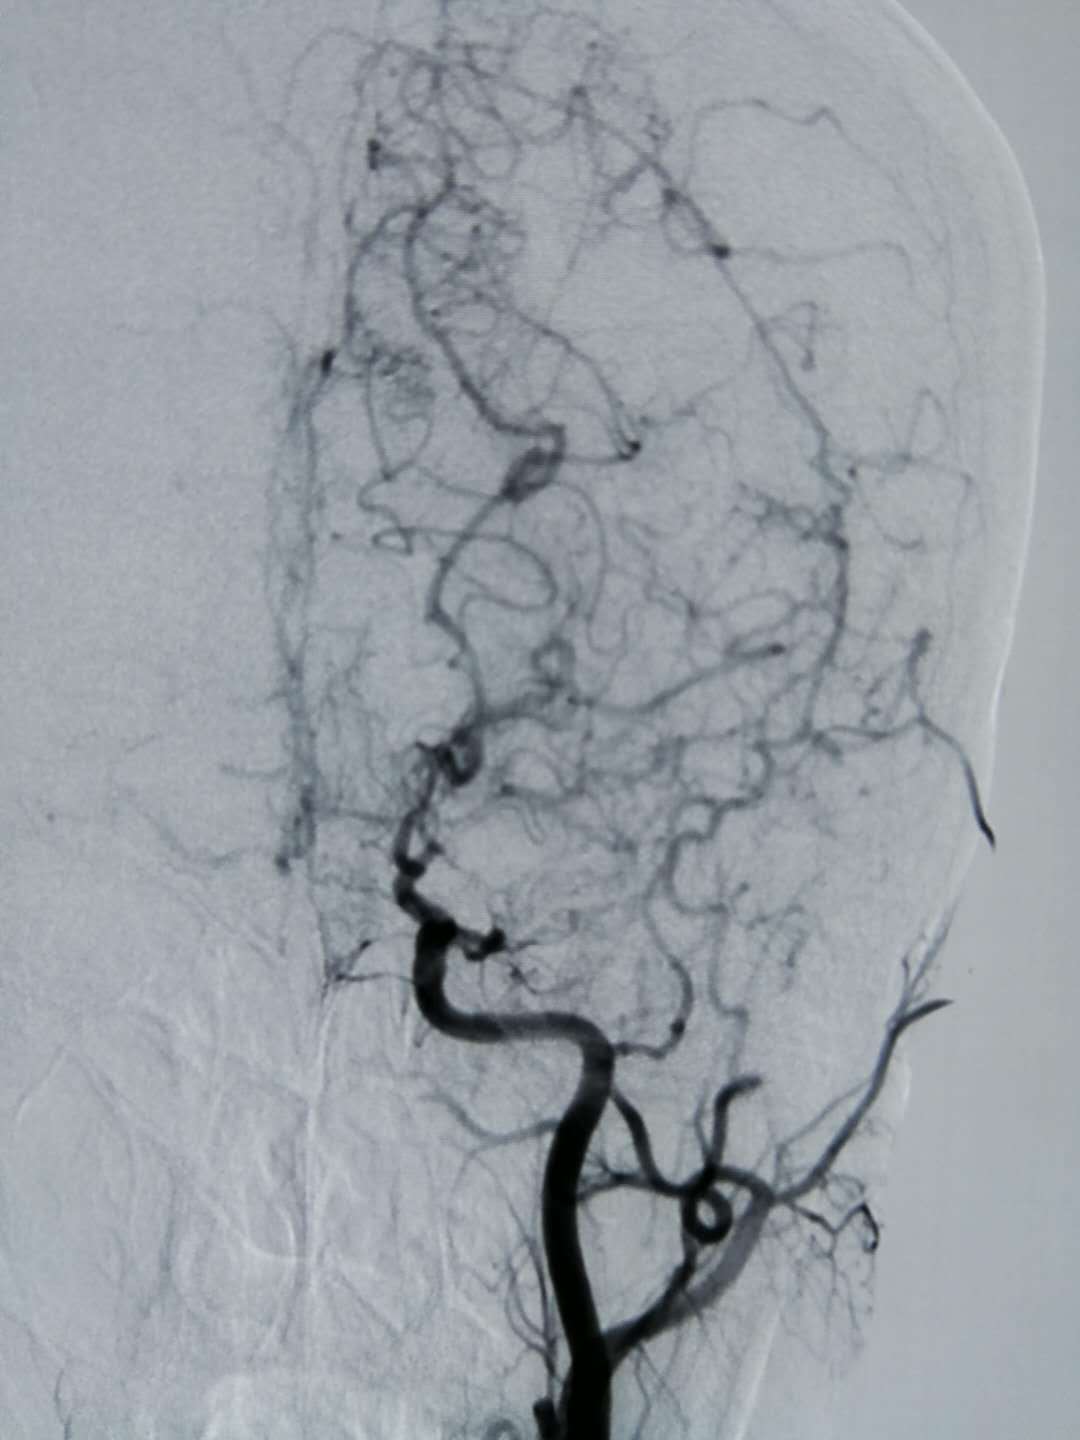

10万个人中只有4个烟雾病患者,如果不幸患上这种罕见病,该如何选择治疗方式呢?

脑血管疾病 烟雾病

突然头晕头痛,肢体无力,说不出话,警惕这种罕见病

烟雾病 脑血管

儿童烟雾病头痛是怎么回事?为什么孩子常常说自己头痛?

脑梗 烟雾病

烟雾病主要影响的是儿童?

烟雾病

烟雾病该做什么检查,不同的检查有哪些意义?

儿童情绪激动手脚发麻,检查发现烟雾病!